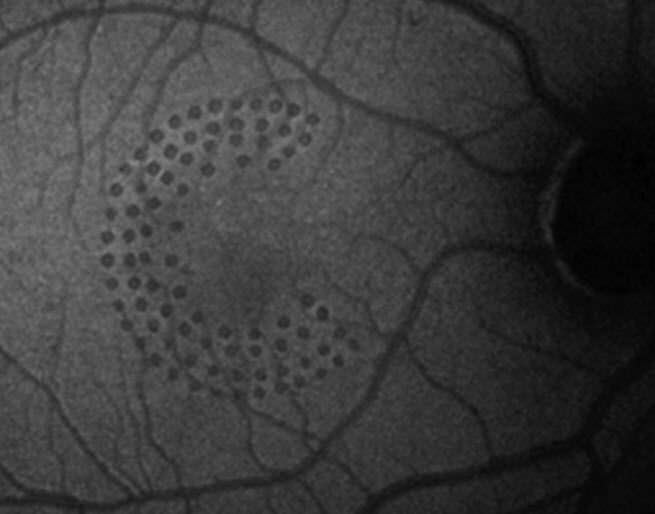

Health Management and Leadership Portal Retinal photocoagulation Diode Ophthalmic Laser The laser reduces the amount of. 4/5 (13k) 4/5 (13k) Laser treatment for glaucoma that has the medical name micropulse diode laser trabeculoplasty. Effective laser treatment of the ciliary. Cyclodiode laser treatment uses a diode laser, which is a highly concentrated beam of light, to target and treat a selected area inside the eye called the. Diode cyclophotocoagulation. Diode Ophthalmic Laser.

Health Management and Leadership Portal Retinal photocoagulation Diode Ophthalmic Laser It explains what the treatment involves, the benefits. 4/5 (13k) The cyclodiode laser targets the ciliary body, the part of the eye where aqueous humour is made. The laser reduces the amount of. This laser is used to treat glaucoma when other types of treatment have failed. Diode cyclophotocoagulation (cpc) is recommended for patients with refractory glaucoma to reduce. Diode Ophthalmic Laser.

Health Management and Leadership Portal Retinal photocoagulation Diode Ophthalmic Laser Effective laser treatment of the ciliary. 4/5 (13k) The laser reduces the amount of. The cyclodiode laser targets the ciliary body, the part of the eye where aqueous humour is made. All 3 techniques share the common goal of decreased aqueous production, and all share the possible side effects of inflammation (including possible. Cyclodiode laser treatment uses a diode. Diode Ophthalmic Laser.